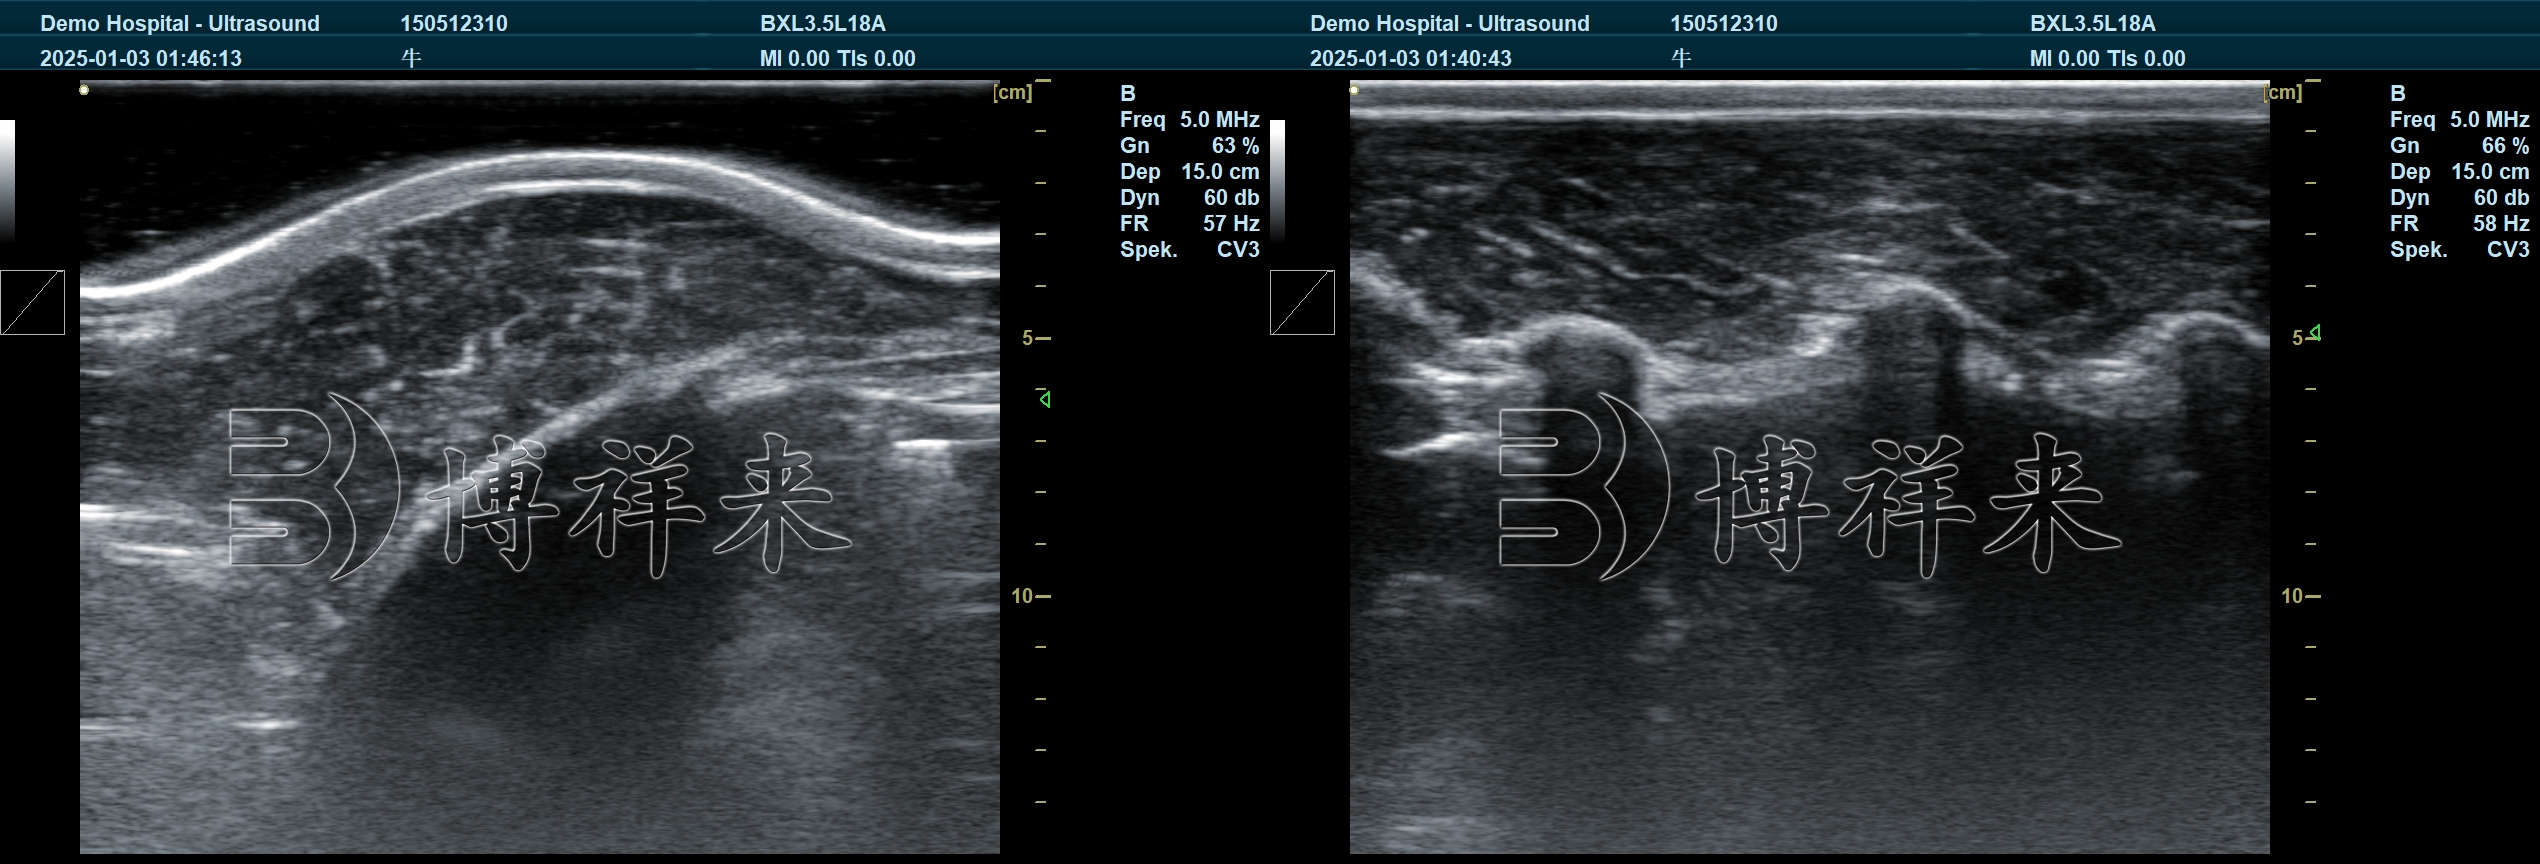

针对肉牛体型大、皮厚脂厚、成像难度高的行业特点,博祥来在背膘仪研发中重点提升了设备的适应性与智能化水平。

其专用探头具备更强的穿透能力与成像清晰度,可准确呈现肉牛脊背脂肪层及眼肌结构,为测量提供可靠基础。

在此基础上,智能AI测量系统能够自动识别眼肌轮廓并计算面积与背膘厚度,大幅降低人工操作误差,提高测量一致性与效率。